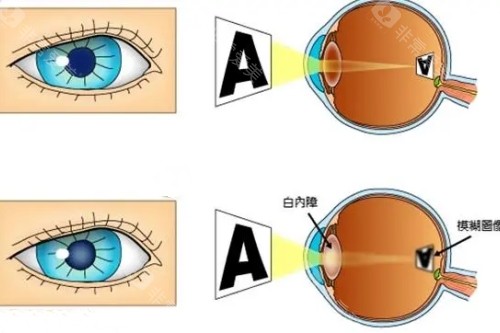

南京医科大学眼科医院提供了丰富多样的医疗服务。它涵盖了常见的眼科疾病治疗,如近视、远视、散光等屈光不正问题,能够为患者提供验光配镜以及各类矫正方案。对于白内障、青光眼等眼科疑难病症,也有相应的诊断和治疗手段。此外,医院还开展了眼部整形美容、小儿眼科等特色服务,满足了不同患者的需求。无论是日常的视力检查,还是复杂的眼部手术,患者都能在该医院找到合适的解决方案。

为了更好地进行眼科诊断和治疗,南京医科大学眼科医院配备了较为齐全的设备。在检查方面,有眼底照相机可以清晰拍摄眼底图像,帮助医生发现眼底病变;验光设备能够比较准测量患者的视力情况。在治疗设备上,有用于白内障手术的超声乳化仪等。这些设备为医生的诊断和治疗提供了有力的支持,有助于提高诊断的比较准性和治疗的结果。